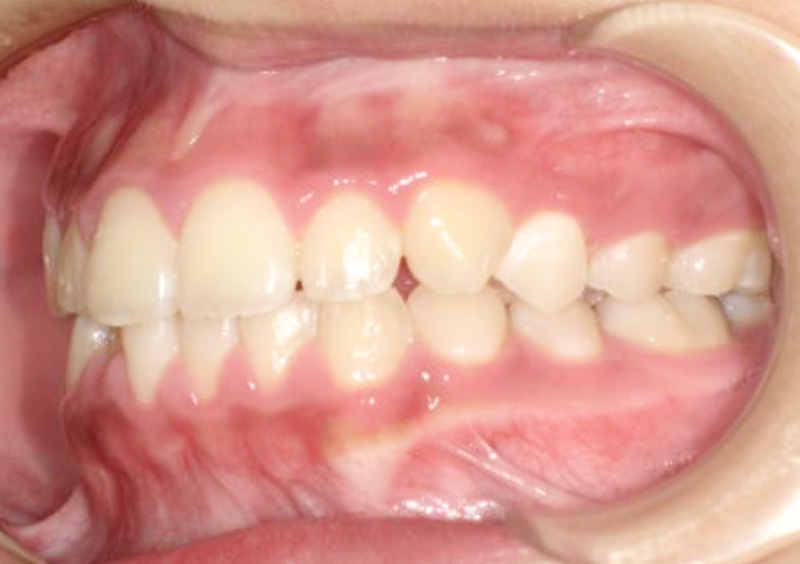

子供の矯正治療 大人の歯が生えてくるスペースがない 2025.10.21 【マルチブラケット矯正】大人の歯が生えてくるスペースがない 治療前 治療後 担当医 一瀬 悠依華 先生 主訴 大人の歯が生えてくるスペースがない 期間 2年3か月 費用 30万円(小児矯正) 治療内容 マルチブラケット装置(ホワイト) 治療に伴うリスク 歯根吸収、歯肉退縮 関連症例